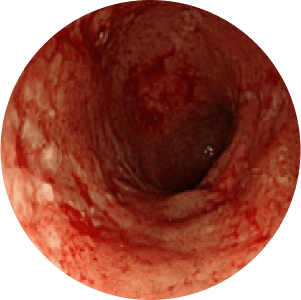

Stages of Ulcerative Colitis

stage

Noraml Mucosa

Mild Inflamation

Modearte Inflamation

Severe Inflamation